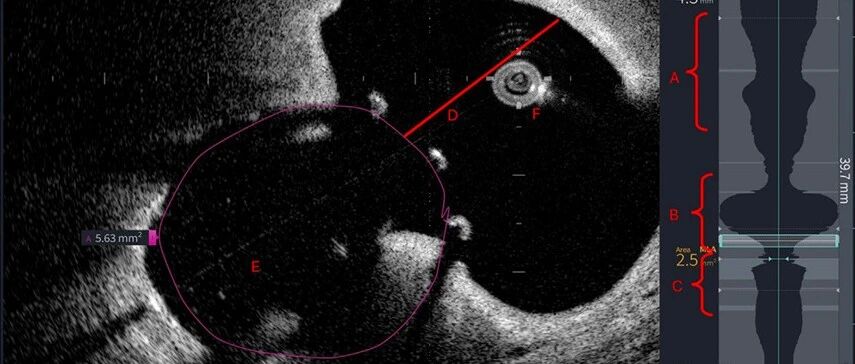

病例 | 高危孕妇重度钙化性二尖瓣狭窄,拒绝终止妊娠且不宜外科手术,介入团队如何破局? 心在线 · 公众号 · · 3 月前 · |